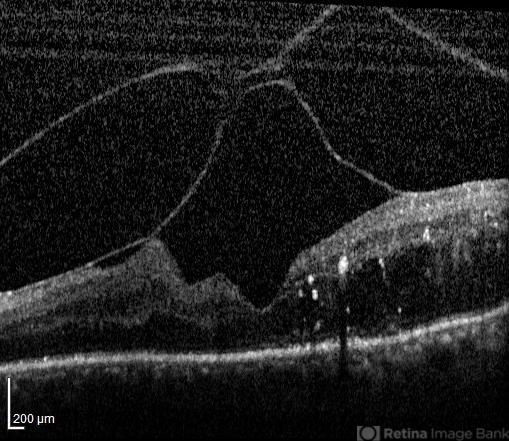

- optical coherence tomography (OCT), vitreoschisis, diabetic macular edema

- Nayereh Hadipour, Negah Eye Center, Tehran

- Optical coherence tomography system

- OCT image of the left eye of a 70-year-old woman with proliferative diabetic retinopathy associated with vitreoschisis and diabetic macular edema. The vitreal changes simulate the appearance of a spider on the retina !